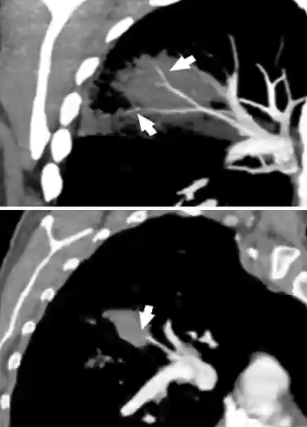

肺血管租塞征

❖ 定义:真菌感染侵袭血管导致血栓形成,造成局限性浸润灶内血管中断,类似于肺栓塞

❖ VOS适用病灶:结节大于10mm,楔形病灶大于12mm

❖ 在粒缺和非粒缺真菌感染患者中,VOS的敏感性和特异性均较高,VOS阴性可以排除一部分真菌感染

❖ 血液系统恶性肿瘤患者中,VOS阳性诊断真菌感染的敏感性和特异性均较其他(HS,RHS,HyS)征象高,VOS阴性提示应停止早期经验性抗真菌治疗